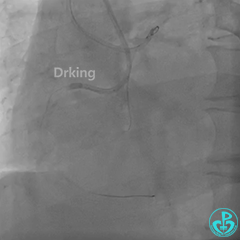

左冠造影:

导丝怎么扩收藏:器械难以通过的CTO病变之技术图谱_https://www.jmylbn.com_新闻资讯_第3张